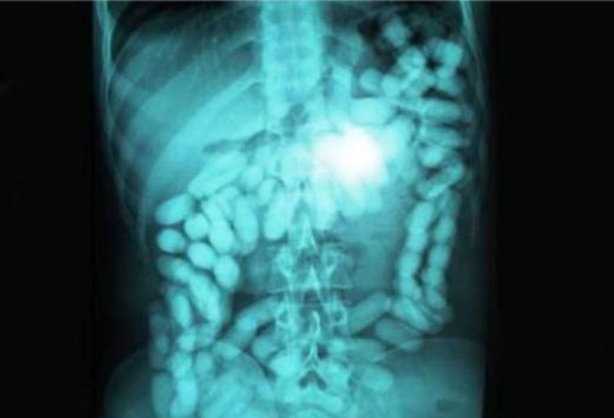

Hollanda'da 52 yaşında bir kadın 78 tane gümüş kaşık yuttu.